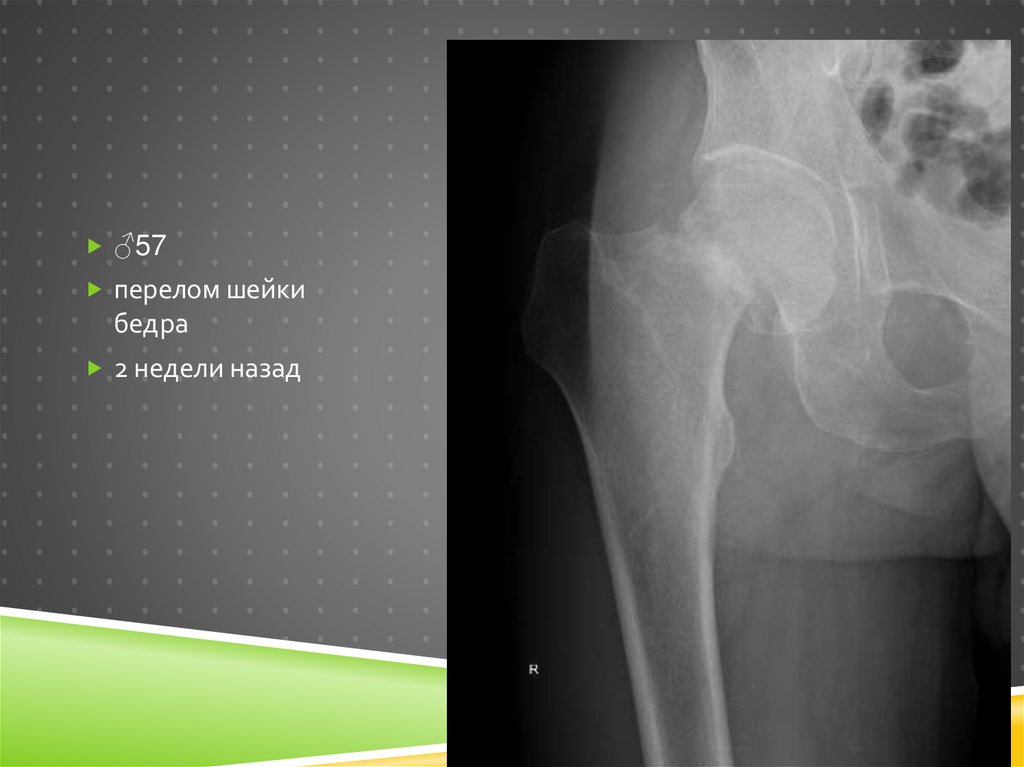

♂57

перелом шейки

бедра

2 недели назад